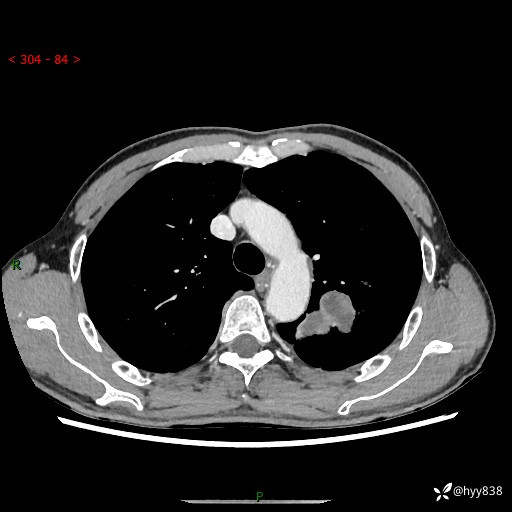

现病史:患者余4月前发现咳嗽咳痰伴痰中带血,无胸闷、胸痛、头晕、恶心、呕吐等不适,2天前因体检发现肺部结节遂于当地市第一人民医院行胸部CT薄层平扫+三维重建示:1.左肺上叶尖后段占位性病变考虑肿瘤性病变伴阻塞性肺炎,右肺上叶后段磨玻璃结节。2.肝内多发囊性灶、左肾结石。现患者为求进一步治疗,于我院门诊就诊,门诊以“肺结节”收入院。 自患病以来,精神、饮食、睡眠尚可,大小便正常,体力体重无明显减轻。

胸部CT增强扫描(外院平扫)